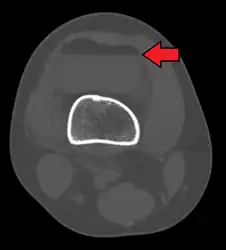

In all injuries to the tibial plateau radiographs (commonly called x-rays) are imperative. Computed tomography scans are not always necessary but are sometimes critical for evaluating degree of fracture and determining a treatment plan that would not be possible with plain radiographs.[6] Magnetic Resonance images are the diagnositic modality of choice when meniscal, ligamentous and soft tissue injuries are suspected.[7][8] CT angiography should be considered if there is alteration of the distal pulses or concern about arterial injury.

3D reconstruction of a CT image of a tibial plateau fracture

Subtle tibial plateau fracture on an AP X ray of the knee

A tibial plateau fracture seen on X-ray